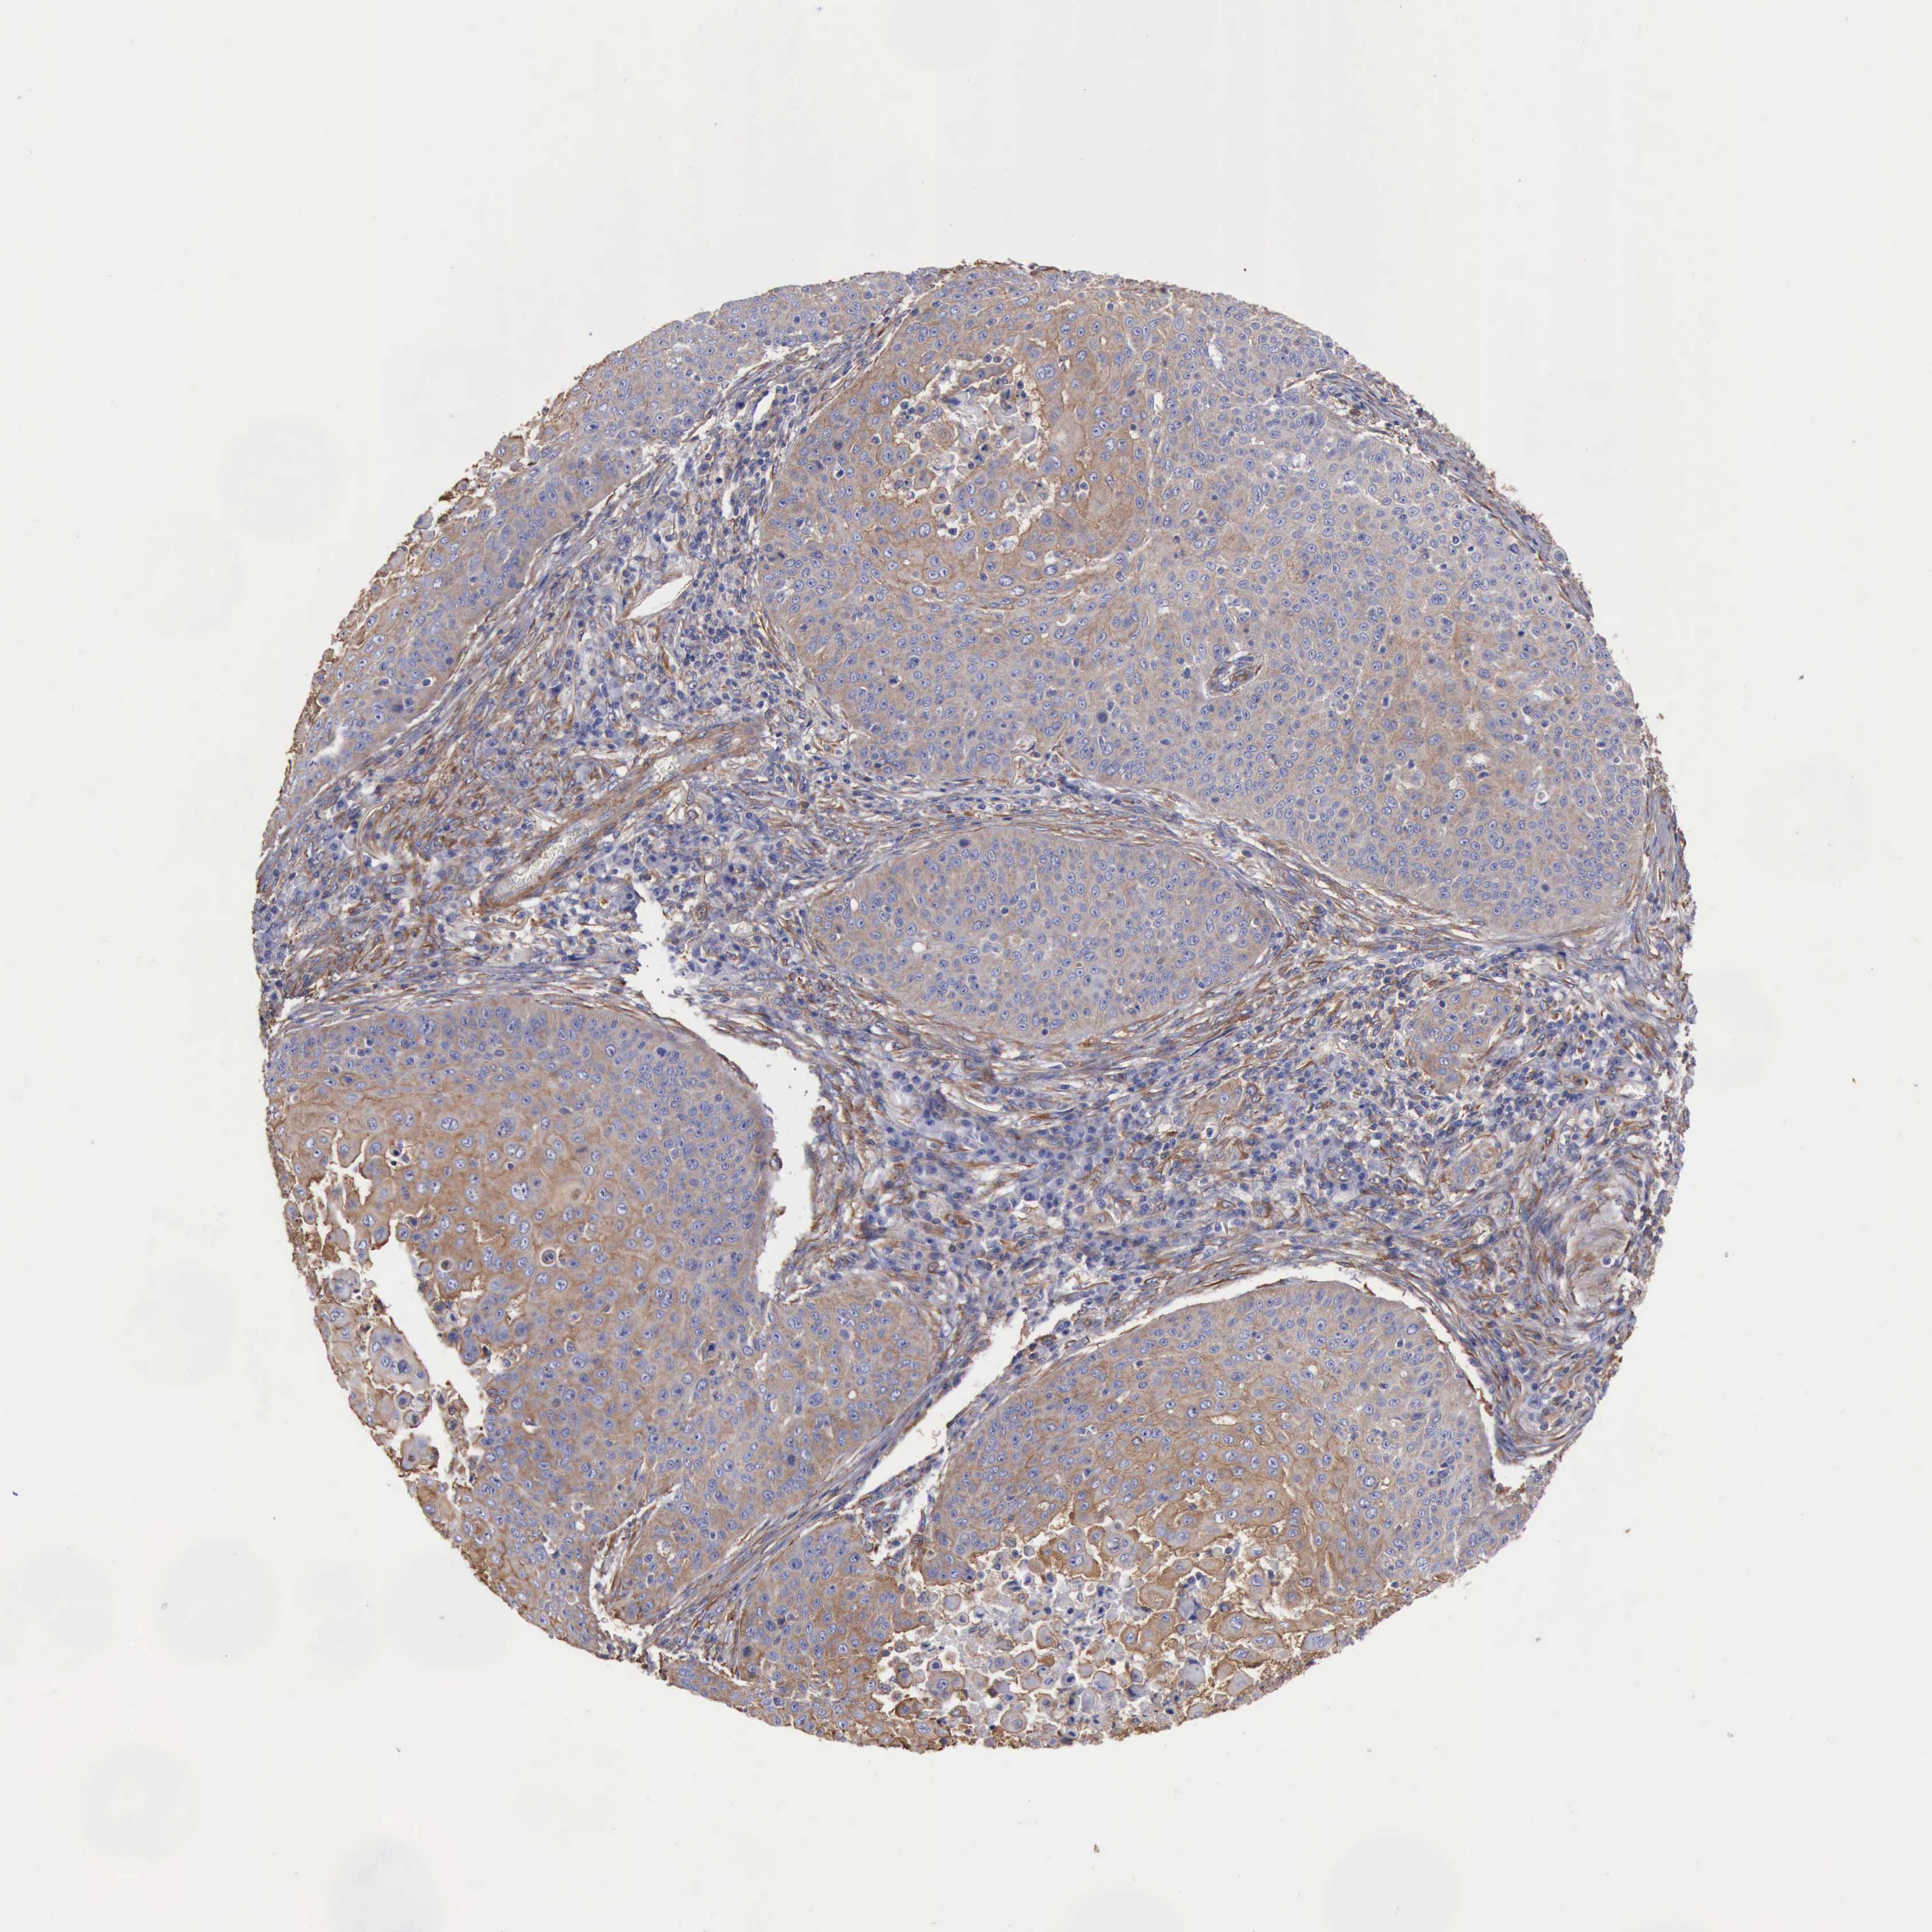

SKIN CANCER - Protein expressioni

A mouse-over function shows sample information and annotation data. Click on an image to view it in a full screen mode. Samples can be filtered based on level of antibody staining by selecting one or several of the following categories: high, medium, low and not detected. The assay and annotation is described here.

Each image is clickable and will lead to virtual microscopy that enables deeper exploration of all samples and also displays staining intensity scores, fraction scores and subcellular localization as well as patient and tissue information for each sample.

Antibody HPA001115

Antibody HPA002925

Antibody CAB000356

Staining

High

Medium

Low

Not detected

Intensity

Strong

Moderate

Weak

Negative

Quantity

>75%

75%-25%

<25%

None

Location

Nuclear

Cytoplasmic/membranous

Cytoplasmic/membranous,nuclear

Squamous cell carcinoma, NOS

Basal cell carcinoma